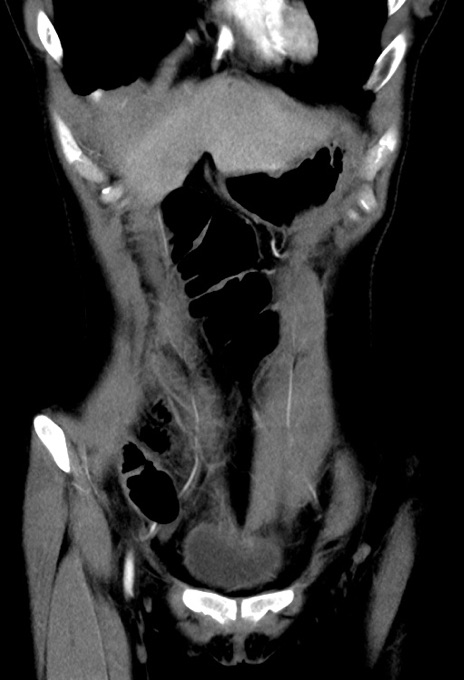

症例17(冠状断像)

【症例】20歳代女性

【主訴】嘔吐、下腹部痛

【現病歴】昨日夕食後に嘔吐し下腹部痛が出現。本日になっても嘔吐持続し改善しないため来院。

【身体所見】意識清明、BT 37.2℃、BP 108/67mmHg、腹部:平坦、やや硬、下腹部正中から右にかけて圧痛あり、反跳痛軽度あり、tapping pain(+)。

【データ】WBC 13600、CRP 14.94